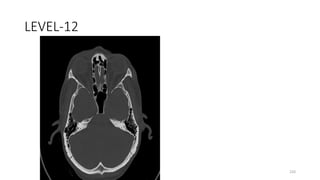

LEVEL-12

233

SQUAMO- OCCIPITO

234

OCCIPITO MASTOID SUTURE

235

POSTERIOR SEMICIRCULAR CANAL

236

BODY SPHENOID

237

GREATER WING SPHENOID

238

SPHENOSQUAMOUS SUTURE

239

PETROUS TEMPORAL

240